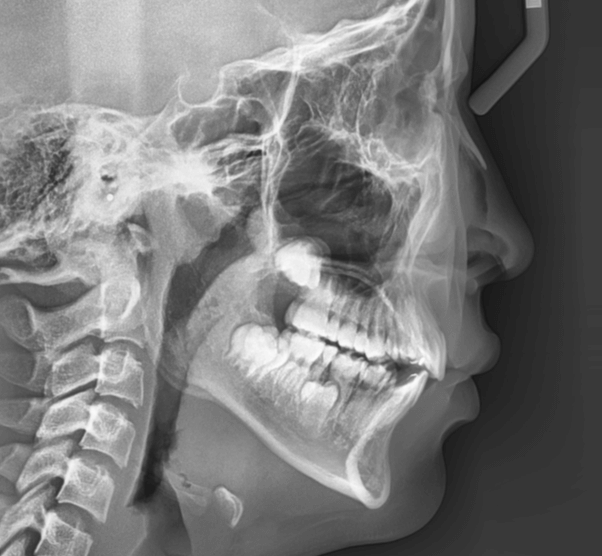

| 年齢・性別 | 8歳9ヶ月の女児 |

|---|---|

| 主訴 | 歯並びの乱れを気にされて来院された患者様です。将来的なスペース不足と歯のねじれ(翼状捻転)が懸念されました。 |

| 治療期間・回数 | 2年10ヶ月・19回 |

| 費用 | 430,000円(税別) |